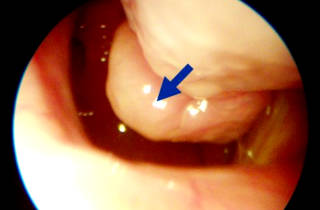

Основным и наиболее эффективным способом диагностики является эндоскопия. Этот метод позволяет точно определить степень и локализацию патологического процесса.

При ринодиагностике наблюдается гиперплазия (утолщение) слизистой оболочки нижнего отдела носа, реже — среднего. Измененные участки могут иметь как гладкую, так и бугристую поверхность. Слизистая оболочка выглядит покрасневшей и слегка синюшной. При утолщении костной основы носовых раковин их размеры не увеличиваются.